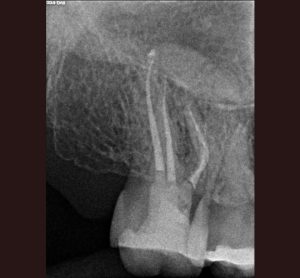

AllAccess Design and ClosureApexificationCBCT DiagnosisCracked TeethCrown Build-upEndodontic MicrosurgeryEndodontic RetreatmentEndodonticsImplantsInternal BleachingMB RootResorption Repair Endodontic Treatment: Case #1- Patient referred due to pain after recent crown cementation. Endodontic Treatment: Case #2 -Patient referred due to pain in her upper first pre molar tooth # 4 Endodontic Treatment: Case #3 – Patient referred due to pain to biting. The amalgam filling was done many years ago. Endodontic Treatment: Case #4 – Patient presented for root canal therapy referred to our office due to complex root anatomy. Endodontic Treatment: Case #5 – Necrotic (dead nerve) tooth with biting pain. Endodontic Treatment: Case #6- Necrotic (dead nerve) tooth with no pain referred for treatment. Endodontic Treatment: Case #7- Very unique tooth with lots of canals (this was a dentists tooth!) Endodontic Treatment: Case #8 – recently prepared for a crown. The patient has cold sensitivity and was referred for treatment. Endodontic Treatment: Case #9- Interesting root anatomy and diagnosis. Endodontic Treatment: Case #10 – 4 canalled lower first molar with 2 distals and 2 mesial canals with a common apex of the mesial root system. Endodontic Treatment: Case #11 Endodontic Treatment: Case #12- Four canalled lower first molar. Finding MB2 The MB Root: Case # 1 The MB Root: Case #2 The MB Root: Case #3 The MB Root: Case #4 The MB Root: Case #5 The MB Root: Case #6 The MB Root: Case #7 The MB Root: Case #8 The MB Root: Case #9 Maxillary MB Root: 1 Mandibular MB Root: 1 Mandibular MB Root: 2 Maxillary MB Root: 2 Mandibular MB Root: 3 Maxillary MB Root: 3 Mandibular MB Root: 4 Endodontic Retreatment: Case #1 – Silver point root canal that was performed 30 years earlier. Endodontic Retreatment: Case #2- Retreatment of initial root canal done 15 years earlier. Endodontic Retreatment: Case #3- Retreatment of a recent root canal performed 2 weeks earlier. Endodontic Retreatment: Case #4 – Retreatment of initial root canal done 12 years earlier Endodontic Retreatment: Case #5 – Retreatment of initial root canal done 30 years earlier. Endodontic Microsurgery: Case #1 Endodontic Microsurgery: Case #2 Endodontic Microsurgery: Case #3 Endodontic Microsurgery: Case #4 Endodontic Microsurgery: Case #5 – Intentional replantation (not so common procedure) Access Closure: Case #1 Access Closure: Case #2 Access Closure: Case #3 Access Closure: Case #4 Access Closure: Case #5 Access Closure: Case #6 Access Closure: Case #7 Access Closure: Case #8 Access Closure: Case #9 Access Closure: Case #10 Access Closure: Case #11 Crown Build-up: Case #1 Crown Build-up: Case #2 Crown Build-up: Case #3 – with bicuspid teeth they are more prone to fracture. Crown Build-up: Case #4 – with bicuspid teeth they are more prone to fracture. Crown Build-up: Case #5 Crown Build-up Case #6 Cracked Teeth: Case #1 Cracked Teeth: Case #2 Cracked Teeth: Case #3 Cracked Teeth: Case #4 Cracked Teeth: Case #5 Cracked Teeth: Case #6 Cracked Teeth: Case #7 Implants: Case #2 Implants: Case #3 Implants: Case #1 Implants: Case #10 Implants: Case #9 Implants: Case #8 Implants: Case #7 Implants: Case #6 Implants: Case #5 Implants: Case #4 CBCT Diagnosis: Case #12 CBCT Diagnosis: Case #11 CBCT Diagnosis: Case #10 CBCT Diagnosis: Case #9 CBCT Diagnosis: Case #8 CBCT Diagnosis: Case #7 CBCT Diagnosis: Case #6 CBCT Diagnosis: Case #5 CBCT Diagnosis: Case #4 CBCT Diagnosis: Case #3 CBCT Diagnosis: Case #2 CBCT Diagnosis: Case #1 High Magnification of Resorption Resorption Repair: Case #5 Resorption Repair: Case #4 Resorption Repair: Case #3 Resorption Repair: Case #2 Resorption Repair: Case #1 Internal Bleaching: Case #3 Internal Bleaching: Case #2 Internal Bleaching: Case #1 Apexification of Lower Premolar